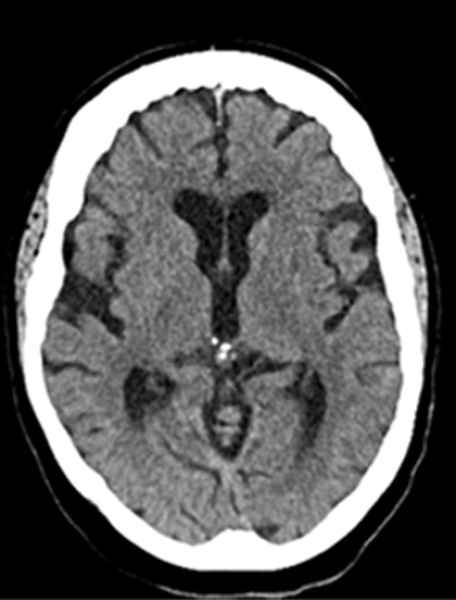

24 h Control CT basal and virtual non contrast

• Follow-up CT showed no hemorrhagic transformation, with only a small established deep left infarct

• At 24 hours, the NIHSS score improved to 3